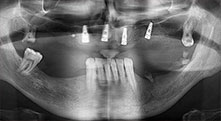

Bratu: We routinely use the instruments for harvesting bone blocks and splitting alveolar ridges. We also use the Piezomed B6/B7 for osteotomy of impacted teeth and removing failed implants. All indications that require deep, clean cuts.

Bratu: We like to use the sandwich technique for augmentation in the lateral mandible. A bone cover is prepared with the piezo saw and the crestal fragment is fixed with microscrews. We place a mixture of autologous bone and xenogenic bone replacement material in between. This works very reliably. You should always ensure sufficiently dimensioned vertical cuts when splitting the alveolar ridge in the mandible. Otherwise the bone may fracture easily.

Bratu: I consider piezo surgery a great leap forward in oral surgery. The technique makes bone preparation safer and easier. Little bone is lost, for example in extractions. This is very important in the aesthetic zone, particularly if immediate implantation is planned. Piezo surgery is also safer for soft tissue: injuries to membranes in the sinus are basically history, as are nerve injuries when bone blocks are being harvested. Data indicating reduced postoperative swelling and pain are also available. Piezo surgery is also ideal for preparation of sinus septa. And last but not least, our patients benefit from the atraumatic nature of this technology.